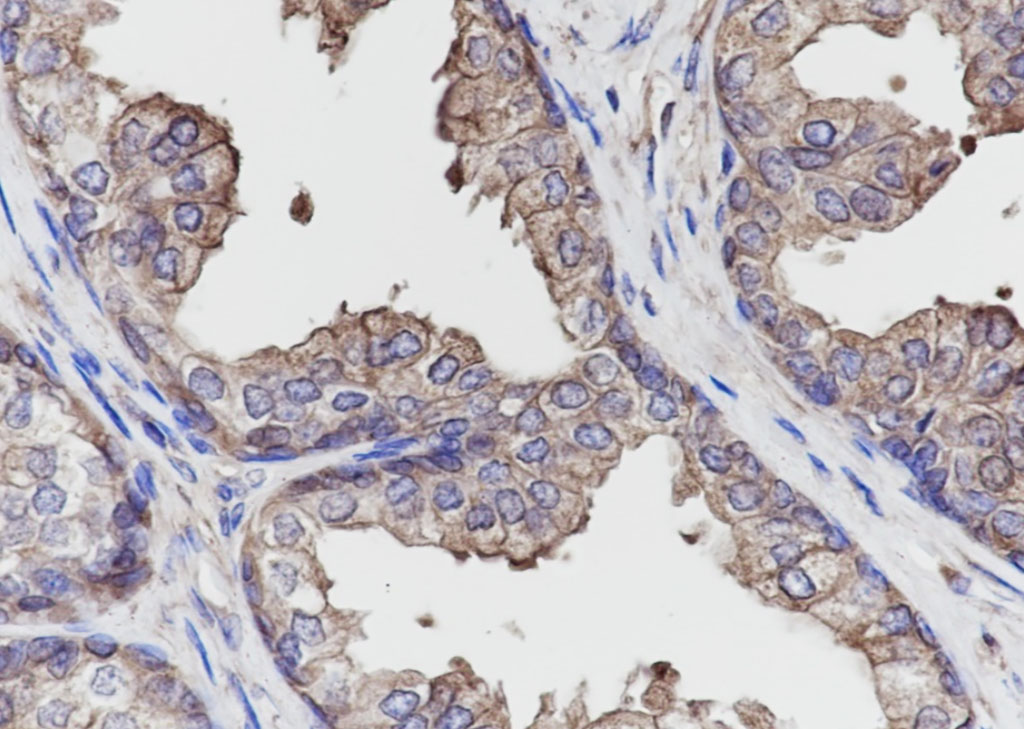

Tissue: Human breast cancer Section type: Formalin fixed & Paraffin -embedded section Retrieval method: High temperature and high pressure Retrieval buffer: Tris/EDTA buffer, pH 9.0 Primary ab dilution: 1:1000 Primary ab incubation condition: 1 hour at room temperature Secondary ab: SP Kit(Rabbit) (sp-0023) Counter stain: Hematoxylin (Blue) Comment: Color brown is the positive signal for bsm-60614R

Tissue: Human prostatic hyperplasia Section type: Formalin fixed & Paraffin -embedded section Retrieval method: High temperature and high pressure Retrieval buffer: Tris/EDTA buffer, pH 9.0 Primary ab dilution: 1:1000 Primary ab incubation condition: 1 hour at room temperature Secondary ab: SP Kit(Rabbit) (sp-0023) Counter stain: Hematoxylin (Blue) Comment: Color brown is the positive signal for bsm-60614R